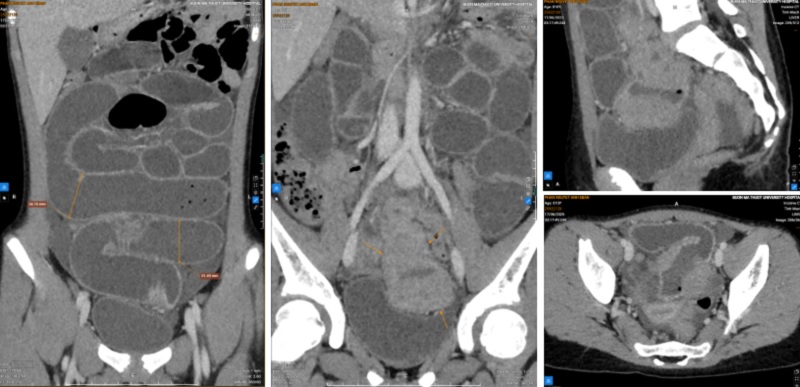

Qua hình ảnh chụp cắt lớp vi tính (CT) ổ bụng. Kết quả thấy hình ảnh rõ ràng hơn tắc ruột non do khối u hồi tràng, nghĩ nhiều đến u lympho, đồng thời phát hiện nhiều hạch ổ bụng và dịch tự do trong ổ bụng.

Hình ảnh trên CT ổ bụng cho thấy tắc ruột non do khối u hồi tràng. Ảnh: BVCC